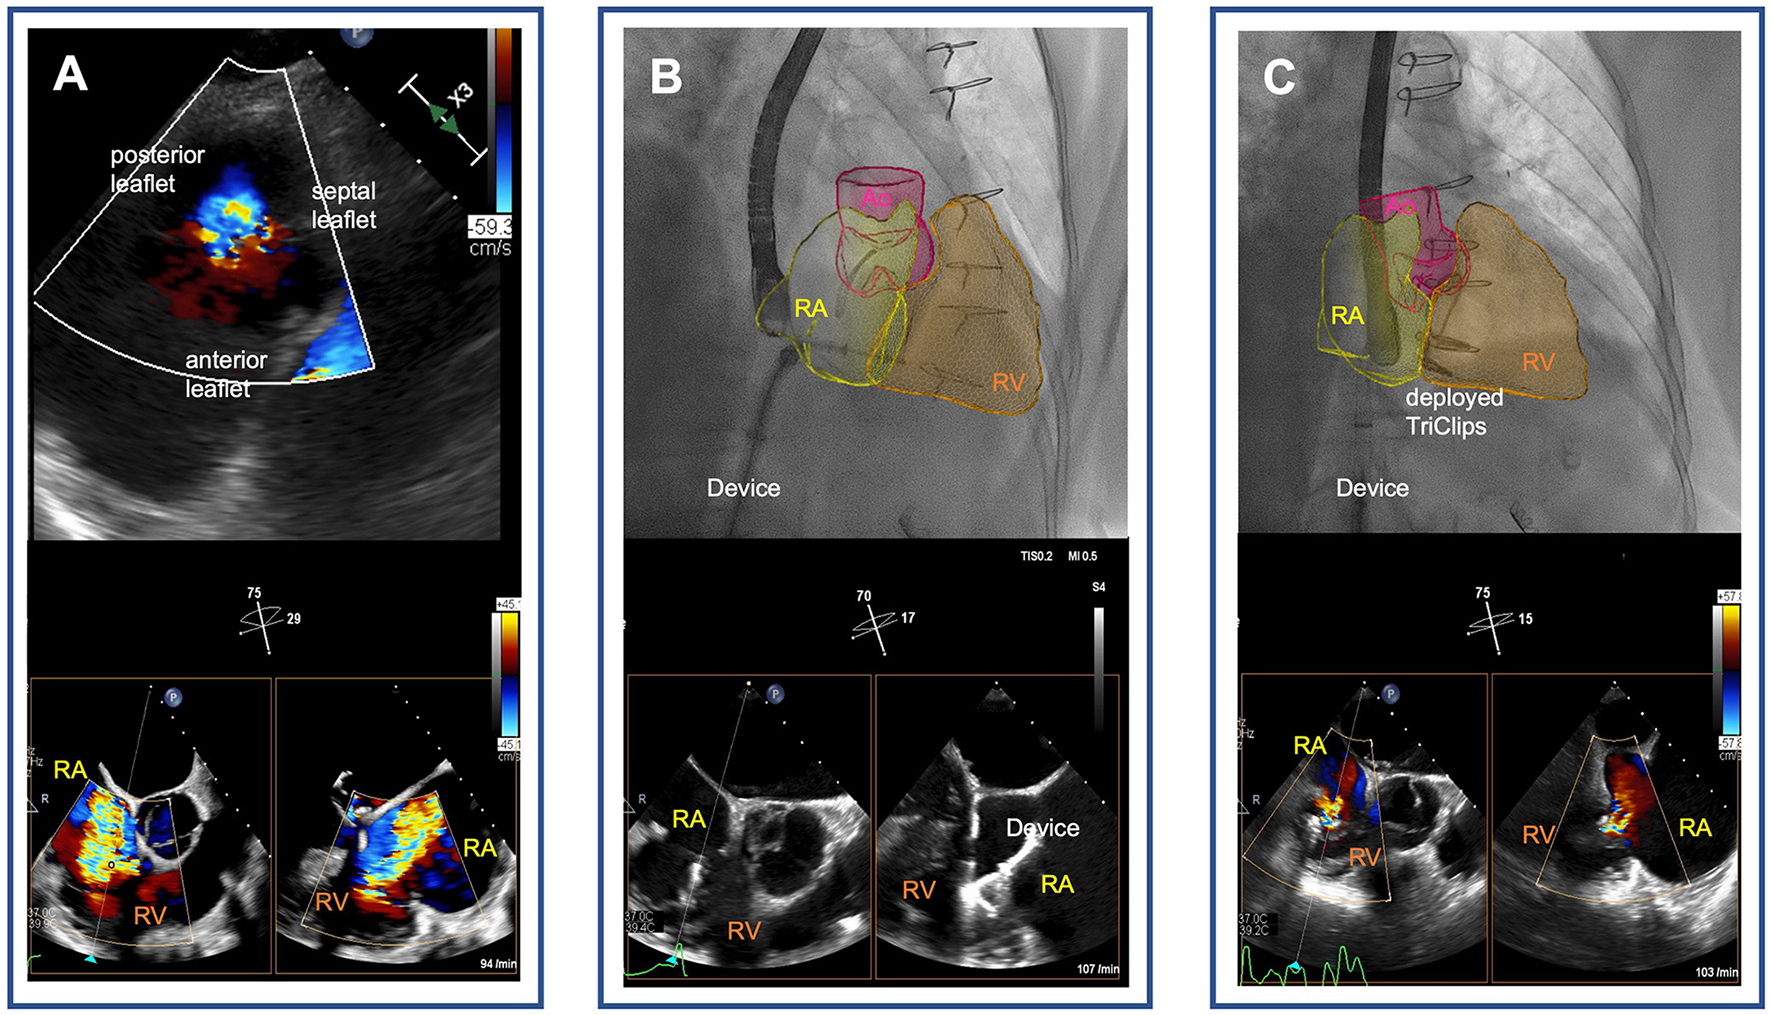

TEER was performed by using the TriClip® device (Abbott, Vascular GmbH). During the TEER procedure, it was difficult to visualize the septal leaflet of the tricuspid valve in transesophageal echocardiography (TEE) due to shadowing from the annuloplasty ring on the mitral site. This was resolved by utilizing an atypically higher degree of probe rotation (Supplementary Video S2). Previous sutured annuloplasty of the tricuspid valve did not affect imaging of the valve or the procedure itself. The first device was used to grasp the anterior and septal leaflets. The second device was deployed to grasp the posterior and septal leaflets. Tricuspid regurgitation was reduced to a mild degree in postprocedural TEE (Figure 1), and in transthoracic echocardiography that was performed at the time of discharge (Supplementary Video S3). Hemodynamic improvement with slightly reduced left atrial pressure (from 12 mmHg before the procedure to 9 mmHg after the procedure) and markedly increased cardiac index (from 1.8 to 2.5 L·min−1·m−2). After 1 month of follow-up, repeat echocardiography demonstrated tricuspid regurgitation grade 1 without stenosis (transvalvular gradient of 1 mmHg). The patient reported that physical capacity and dypnea had improved (to NYHA functional class I).

Figure 1

Tricuspid transcatheter edge-to-edge repair following surgical tricuspid annuloplasty. (A) Severe functional tricuspid regurgitation following sutured annuloplasty [transgastric view on the tricuspid valve (upper panel) and biplane transesophageal echocardiographic images of the right ventricular outflow tract (lower panel)]. (B) Real-time fusion imaging-assisted navigation of the transcatheter tricuspid valve repair device through the right atrium pointing to the tricuspid annulus (upper panel). Biplane transesophageal echocardiographic images of the right ventricular outflow tract showing grasping of the septal and anterior leaflets of the tricuspid valve with the TriClip device (lower panel). (C) Mild tricuspid regurgitation after deployment of two TriClips [real-time fusion of echocardiography-derived right heart cavities on fluoroscopy visualizes the TriClips (upper panel), and biplane esophageal echocardiographic image demonstrates reduction of tricuspid regurgitation to mild degree (lower panel)]. RA, right atrium; RV, right ventricle; Ao, aortae.